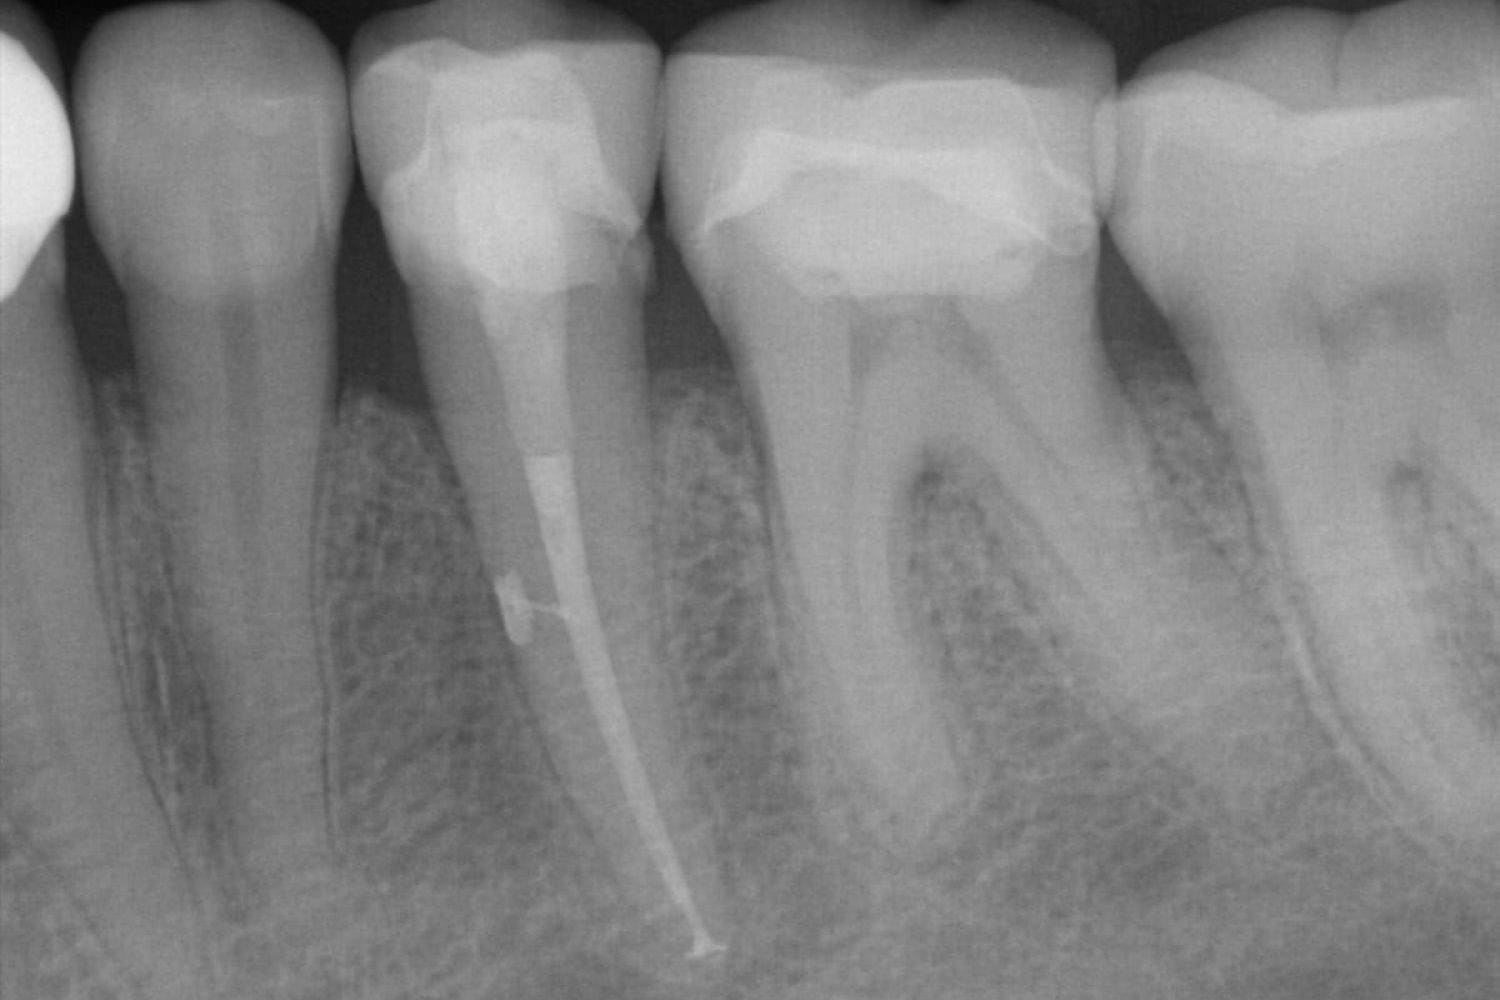

Bei der Wurzelkanalbehandlung wird der Zahn geöffnet (trepaniert) und die mikroskopisch kleinen Wurzelkanäle von erkranktem, infiziertem oder totem (devitalem) Weichgewebe befreit. Zudem gesäubert, desinfiziert und ggf. medikamentös versorgt. Eine endometrische Messung sorgt für eine exakte Bestimmung der Aufbereitungslänge und erspart eine Röntgenaufnahme. Ist der Zahn bakterien- und symptomfrei können die Wurzelkanäle des endodontisch aufbereiteten Zahnes gefüllt bzw. versiegelt werden. So wird einer erneuten Entzündung des wurzelspitzennahen Knochens vorgebeugt. Abschließend muss der Zahn adhäsiv verschlossen werden. Dies ist besonders wichtig, um eine Reinfektion zu verhindern. Darüber hinaus dient die Adhäsiv-Klebetechnik der Stabilisierung des Zahnes. Häufig ist auch eine spätere Überkronung notwendig, um die Gefahr einer komplizierten Fraktur zu verhindern.

Eine moderne Wurzelkanalbehandlung ermöglichst sogar die Füllung von Seitenkanälen.

Die Revision ist besonders aufwendig, da hier zunächst eine alte Wurzelfüllung entfernt werden muss. Notwendig ist eine solche Behandlung, wenn der Zahn – trotz einer bestehenden Wurzelfüllung – Entzündungszeichen aufweist (Klopf- / Aufbissempfindlichkeit, Schwellung, Fistelgang, Abszesse) oder eine chronische Entzündung (ohne Schmerzen) auf dem Röntgenbild zeigt. In allen Fällen liegt hier eine bakterielle Infektion des Knochens vor, hervorgerufen durch eine insuffiziente Wurzelfüllung (undicht, Wurzelkanal nicht gefüllt, verbliebenes totes Gewebe, etc.).